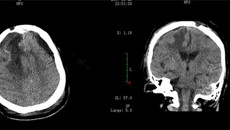

近日,一附院外六科(神经外科)成功进行1例颅底巨大廉旁脑膜瘤开颅显微切除术,肿瘤大小达9.2cm×7.5cm×7.9cm,接近一成年男子拳头大小,在广西区内实属罕见。 患者因“反复头晕10余年,加重并持续全身抽搐1天”由外院转入。入院诊断为:1.右侧大脑半球巨大脑肿瘤;2.继发性持续性癫痫;3.高血压病Ⅲ级,极高危组;4.Ⅱ型糖尿病;5.全身多处皮肤Ⅱ度烫伤。入院后主治医生迅速给予降颅内压、抗癫痫、控制血压...03.292017